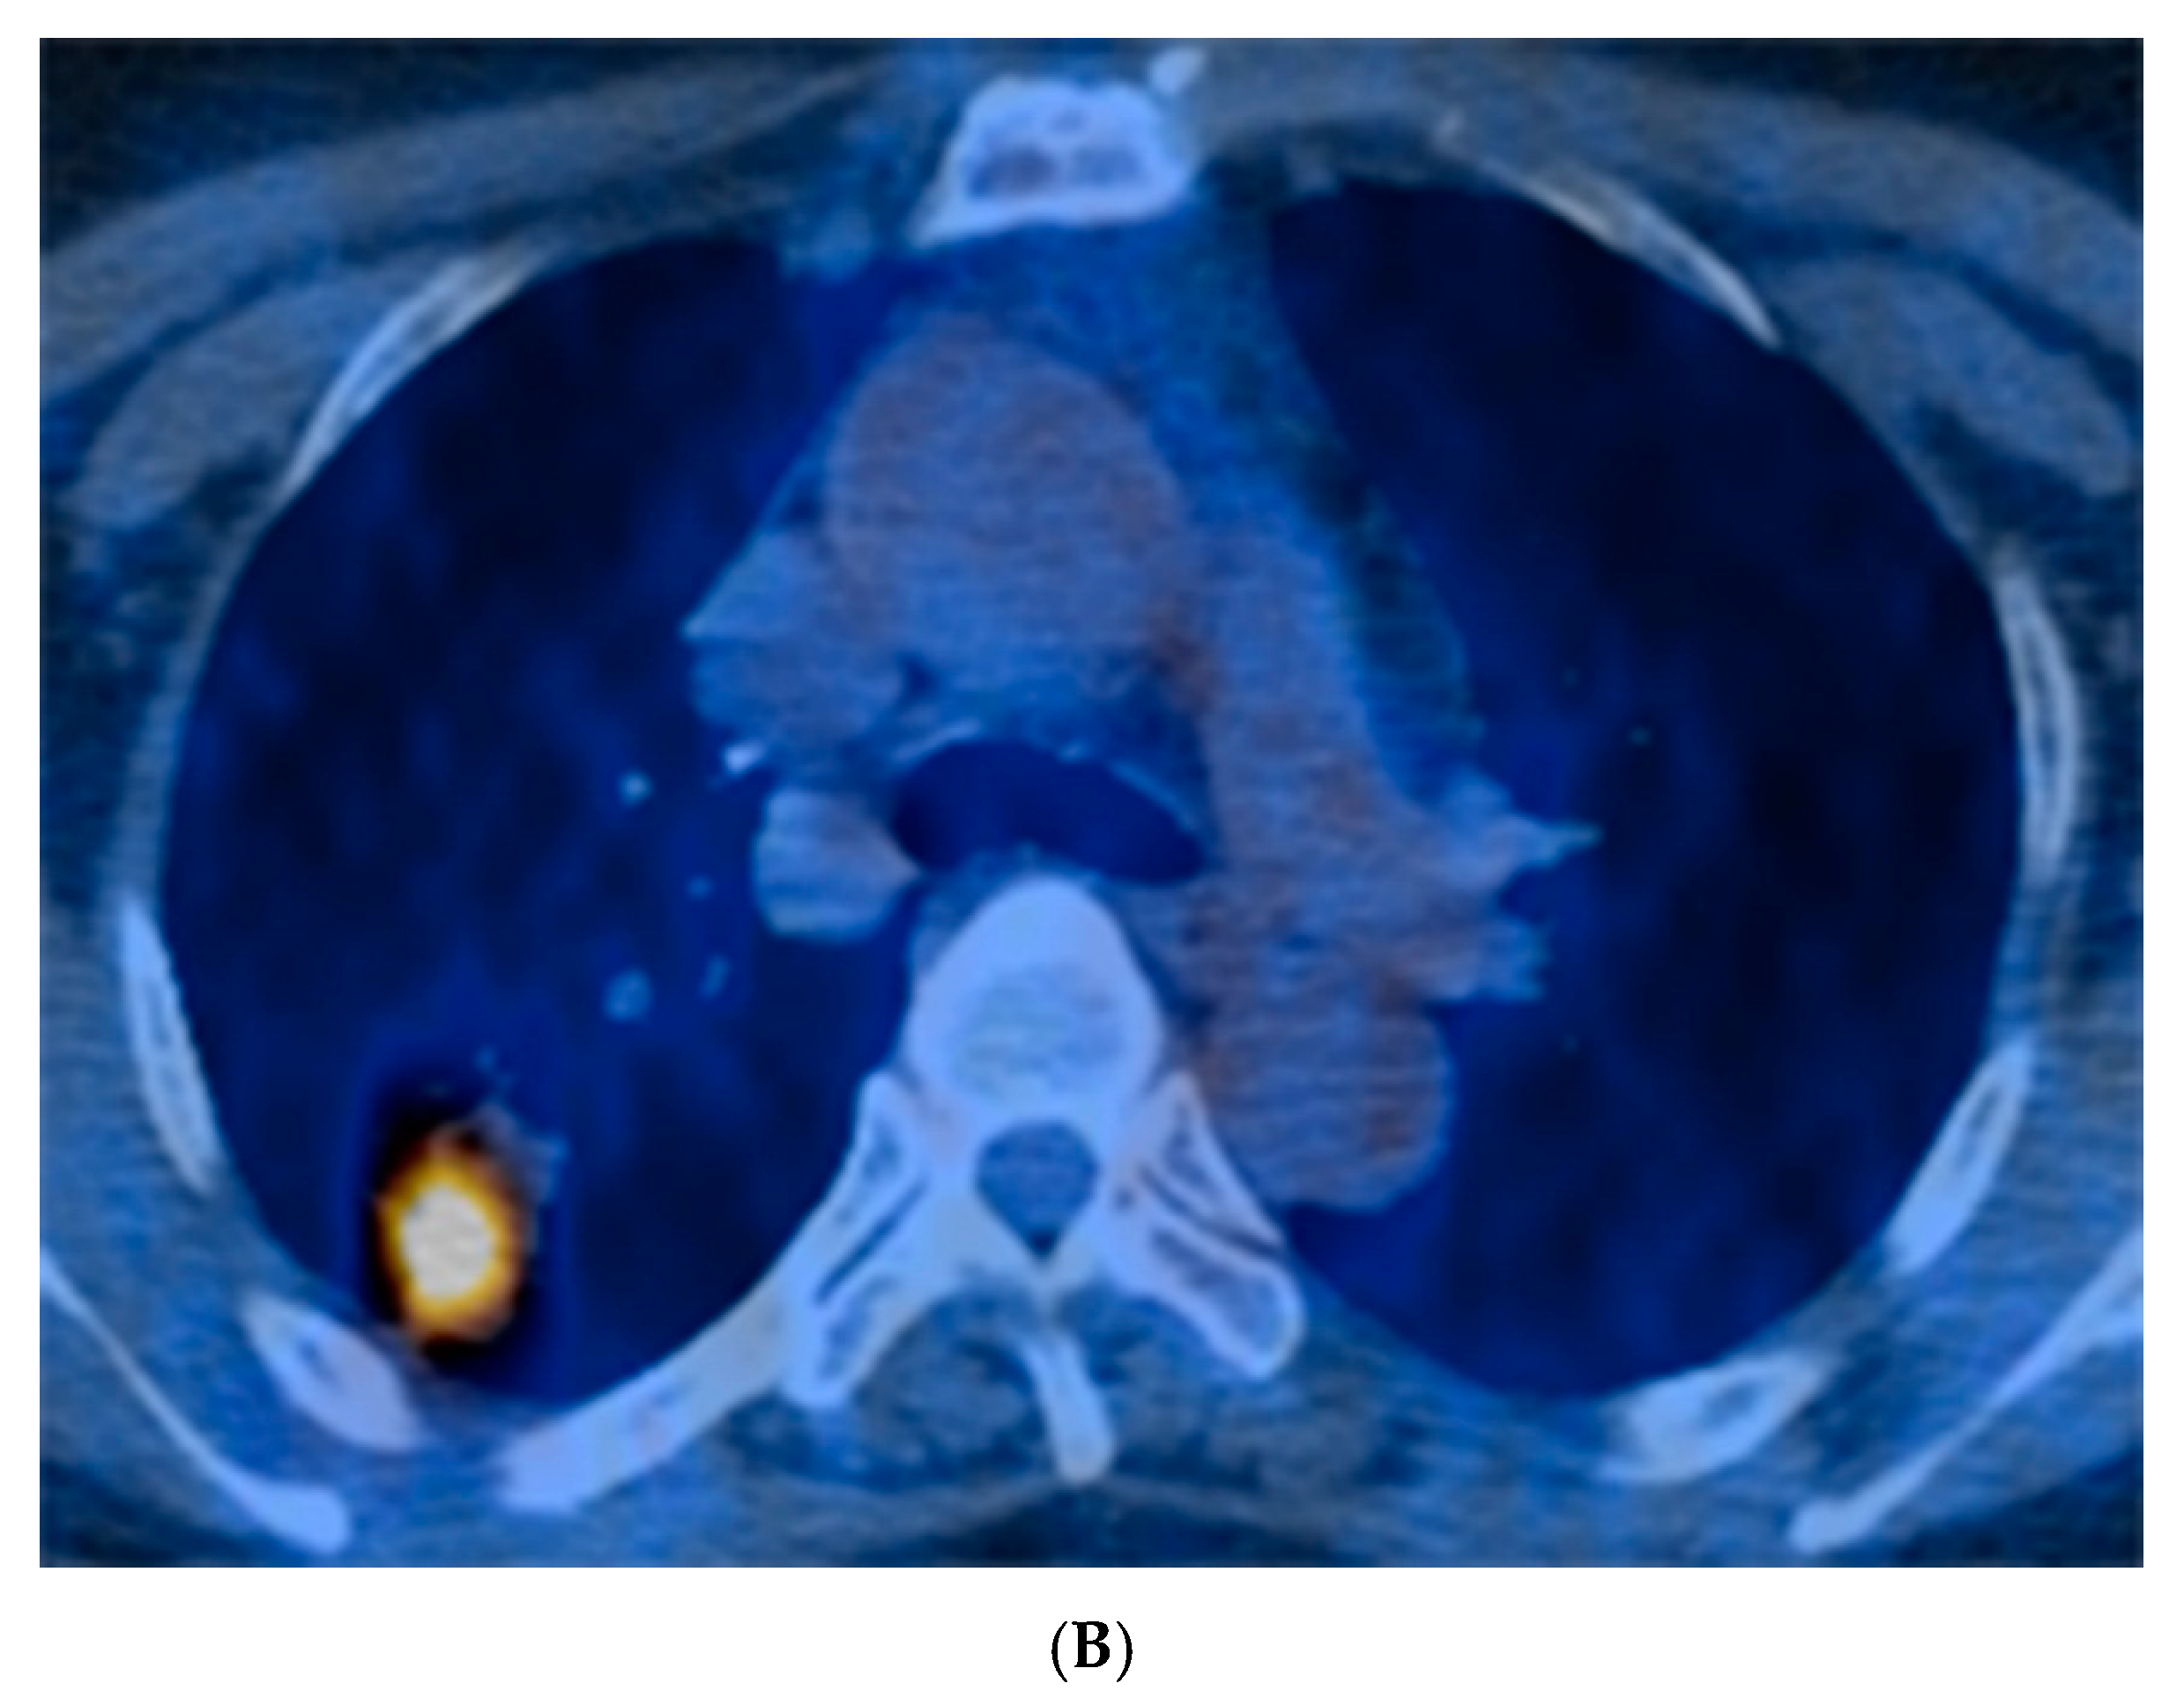

Radiologic characteristics of NTM nodules are summarized in Table 2. The median long-axis diameter of 49 nodules on chest CT was 18.0 mm (IQR 12.5–28.5 mm), and approximately half (49%) were located in the upper lobes. Most (82%) were located in the subpleural area (Figure 1A). Spiculation and pleural invagination were observed at 80% and 73% of the nodules, respectively. About a third of the nodules (31%) had associated calcification and 3 (6%) had satellite lesions. Of the 41 nodules for which FDG-PET/CT was available, the median SUVmax was 4.9 (IQR 2.5–8.7), and 76% (31/41) of them had relatively high uptake (SUVmax > 2.5) (Figure 1B).

Figure 1.

(A) A 56-year old female with a solitary pulmonary nodule. Chest computed tomography showed a 23-mm-sized oval nodule at the posterior segment of right upper lobe. (B) Positron emission tomography with fluorodeoxyglucose (FDG) revealed a nodule with increased FDG uptake in the right upper lobe mimicking malignancy.

In our study, more than three-fourths (76%) of NTM SPNs showed high SUVmax uptake on FDG-PET/CT scan, which suggests that FDG-PET/CT is likely not useful for differentiating NTM SPNs from malignant nodules. NTM SPN is a unique phenotype of NTM-PD that is frequently difficult to radiologically distinguish from malignancy. However, FDG-PET can be used to evaluate the glucose metabolism of SPNs and thereby identify an active lesion regardless of whether the lesion is benign or malignant. Granulomatous nodules such as tuberculomas or NTM SPNs can have positive results as shown in our previous study that compared characteristics of tuberculomas and NTM SPNs [7]. Although the criteria for distinguishing malignancy vary among researchers, most NTM SPNs showed relatively high FDG-PET uptake in previous studies [18,19].